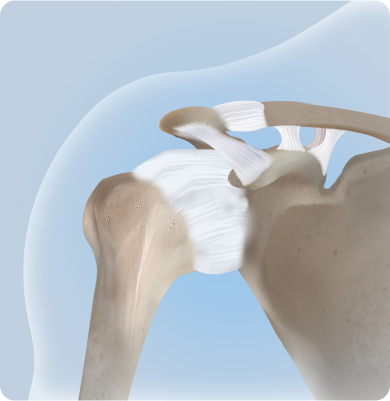

회전근개파열

어깨 관절을 감싸고 있는 회전근개 힘줄이 손상되거나 찢어지는 질환

주요증상

• 팔을 들어 올릴 때 어깨가 찢어지는 듯한 심한 통증이 있습니다.

• 팔을 움직일 때 힘이 빠지거나 떨어뜨릴 것 같은 불안정함이 있습니다.

• 팔을 위로 들거나 뒤로 돌리기 어렵습니다.